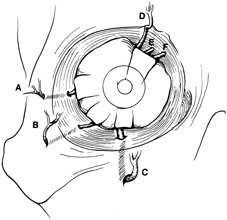

obtain the maximum amount of information from the orbitotomy. Incisions around the orbit are planned with two key considerations in mind. The first is to allow the most direct access to the lesion, and the second is to allow optimal scar camouflage. Incisions may be hidden by placing them within the hairline or brow, in the bulbar conjunctiva, or in the palpebral conjunctiva of the lower lid. A1ternatively, external incisions may be disguised by placing them in preexisting upper or lower eyelid creases, or in lateral canthal rhytides (Fig. 3). Adequate exposure begins with marking the appropriate conjunctival or skin incision. The majority of conjunctival incisions heal without visible scar tissue. However, every skin incision leaves a somewhat visible scar. Thus, there is a tendency to mark as small a skin incision as possible. In some cases, the incision is too small to adequately expose the orbital mass. Hesitation in making a long enough skin incision can be minimized by camouflaging skin incisions as described. Once the skin incision is marked, local anesthetic containing 1:200,000 epinephrine is injected into the adjacent skin. This is done before the surgeon scrubs so that there is sufficient time for vasoconstriction to occur before the skin incision is made. While the surgeon scrubs, the operating room personnel prepare and drape the patient. Because many orbitotomies are performed with the assistance of ophthalmic nurses, there is a tendency to drape an inappropriately small operating field. The operating room staff should be instructed to prepare and drape a generous surgical field. It is usually helpful to prepare and drape both orbits within the field so that the contralateral side may be used as a reference to judge symmetry. Skin incisions usually are made with a No. 15 scalpel blade or a Colorado microdissector needle. Although an adequate-length incision should be made, it is often surprising how extensively the deeper structures can be exposed through a small skin incision when there is wide elevation and retraction of deeper soft tissues overlying the periosteum. If the choice of incision or length of incision is inadequate, the surgical plan should be modified to allow appropriate exposure. Often it is possible to start with a shorter incision, lengthening it if it restricts access. Visualization of deeper orbital tissues involves appropriate retraction of overlying soft tissues. Individual 4-0 silk sutures placed in the subcutaneous tissues offer a large degree of flexibility in retracting the skin and subcutaneous tissues. A variety of orbital retractors should be available for each case. The value of an experienced assistant to provide adequate retraction and exposure cannot be overemphasized. |